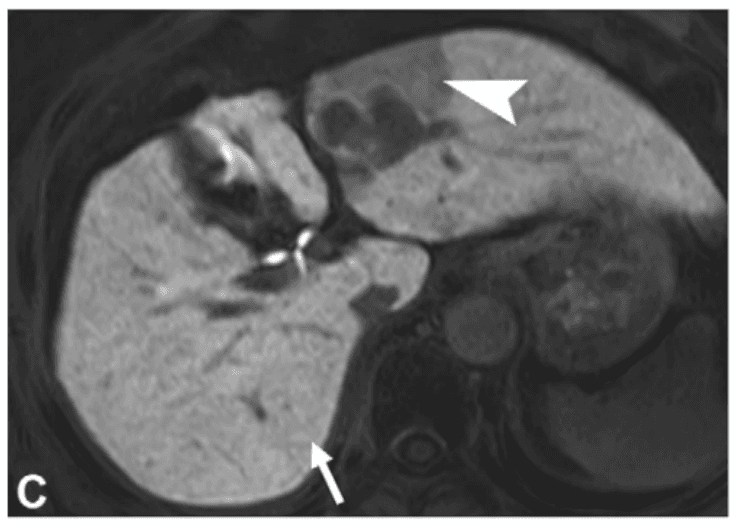

MERIS combina variables clínicas y radiológicas con peso pronóstico claro: AST > 29.5 IU/L (+2), tamaño tumoral en centímetros (+1 por cm), margen tumoral no liso (+2) e hipointensidad peritumoral en fase hepatobiliar (+3). Juntas, estas variables permiten construir un riesgo individualizado de recurrencia temprana y distinguir tumores aparentemente pequeños pero biológicamente agresivos.

La hipointensidad peritumoral en fase hepatobiliar es el hallazgo más robusto del modelo. Su presencia sugiere alteración de transportadores OATP vinculada a obstrucción de vénulas portales por células tumorales. En términos clínicos, es una señal funcional de invasión microvascular antes de que ésta sea visible al microscopio.